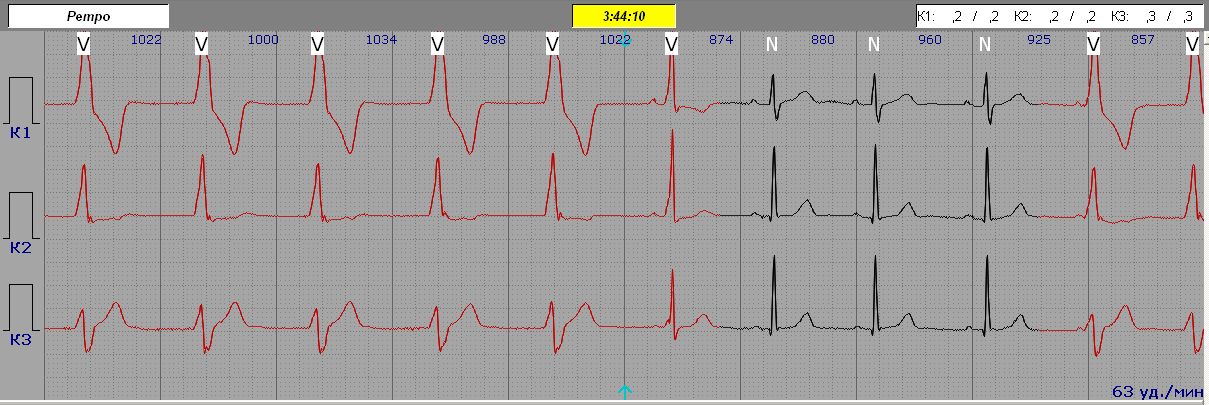

Slow Ventricular Tachycardia (Idioventricular Tachycardia) - (VTS)

QRS komplekss ir izkropļots un garāks par 120 ms.

Pakāpeniska sākšanās un pakāpeniska vājināšanās (pamatojoties uz QRS deformāciju).

R-R intervāli ir vienādi.

Sirdsdarbības ātrums 100–140